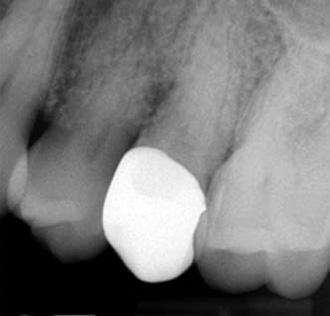

5. a–l. ábrák: Az incisális élen keresztül kialakított hozzáférés lehetővé teszi a pericervikális dentin megőrzését. Kalcifikáció esetén CBCT-felvétel készítése hasznosnak bizonyulhat a hozzáférési nyílás tervezése során (a–d) . Minden fog koronai helyreállítása a gyökértömés elkészítésével egyidejűleg történt. A négyéves (e–h) és a kétéves (i–l) kontrollok alkalmával készített röntgenfelvételeken teljes gyógyulás látható. Mindkét fog tünetmentes és funkcióképes volt. (Dr. Viraj Vora esetei)

zésére. Ez azért fontos, mert a frontfogak funkcionális megterhelése során – a PCD-nek megfelelően elhelyezkedő területben – jelentős stressz ébred (5. a–l ábrák) 24 Szükség esetén egy CBCT-felvételt is készíthetünk. A 3D-s adatok jelentős mértékben segíthetik a klinikus munkáját a gyökércsatorna koronális vetületének vizualizálásában, és ennek alapján az egyenes vonalú hozzáférés biztosításához szükséges belépési pont meghatározásában (5.